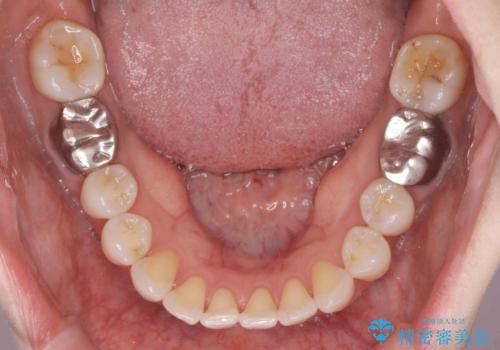

抜歯をせず前歯の角度を改善するマウスピース矯正治療

- 突き出た前歯の角度を改善したい、と矯正治療を希望され来院されました。

治療期間が約半年で行うことができ、歯を抜かずにマウスピース矯正で可及的に前歯の角度を改善する治療方針を

奥歯の状態等も鑑みて選択されました。

約半年で大きく前歯の角度を改善することができ、抜歯を行わない矯正治療の結果に大変喜んでいただくことができました。